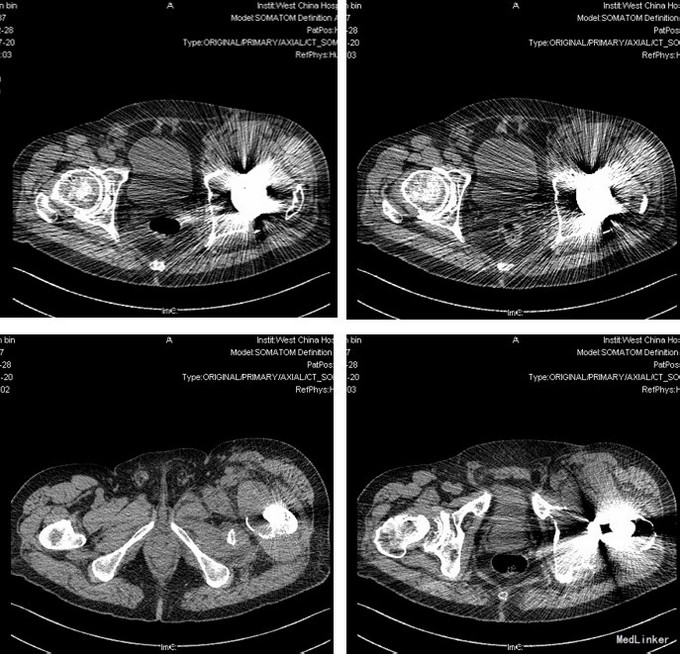

诊断:1.左侧THA术后假体松动、聚乙烯内衬磨损、炎性假瘤形成 2.左侧THA术后髋臼及股骨近端骨溶解 3.左侧THA术后髋臼及股骨近端骨缺损(髋臼AAOS III型 股骨Paprosky II型) 4.右髋重度骨关节炎 5.高血压 (2期 高危) 治疗:完善检查,调整患者全身条件后在全麻下行左侧全髋关节假体取出+炎性假瘤切除+异体骨植骨+髋臼重建+人工全髋关节翻修术,术中发现:左髋关节囊后外侧炎性假瘤形成,与关节腔相通,内有大量咖啡色混浊液体,髋臼及股骨近端骨溶解导致骨缺损,以髋臼前壁及下壁和股骨近端严重,小转子消失,关节腔周围大量炎性坏死组织。髋臼假体松动。术中安放左侧Zimmer64mmCage,并用8枚不同长度螺钉固定可靠,Cage内放骨水泥后安放外径59mm,内径28mm聚乙烯内衬并调整前倾及外展角度合适,股骨侧安放12#加长股骨柄,28mm直径、+1.5颈长陶瓷股骨头。